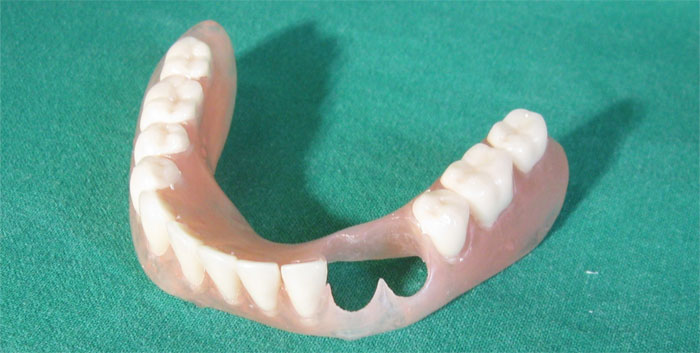

Unterkiefer

Im Februar wurden die Zähne 43 und 44 gezogen (links auf dem Röntgenbild), am selben Tag wurde eine vorläufige metallfreie Kunststoffprothese der Marke DEFLEX gefertigt. Ende Mai 2012 wurde eine herausnehmbare IVOCLAR-Stegprothese auf zwei Teleskopkronen gesetzt.